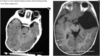

A 12-year-old African-American male with a history of asthma presents with fever, lethargy, seizure activity, and left hemiparesis.

Inflammatory markers are elevated. After stabilization, a CT head with contrast is obtained (figure). What is the most appropriate next

step in management?

Craniotomy